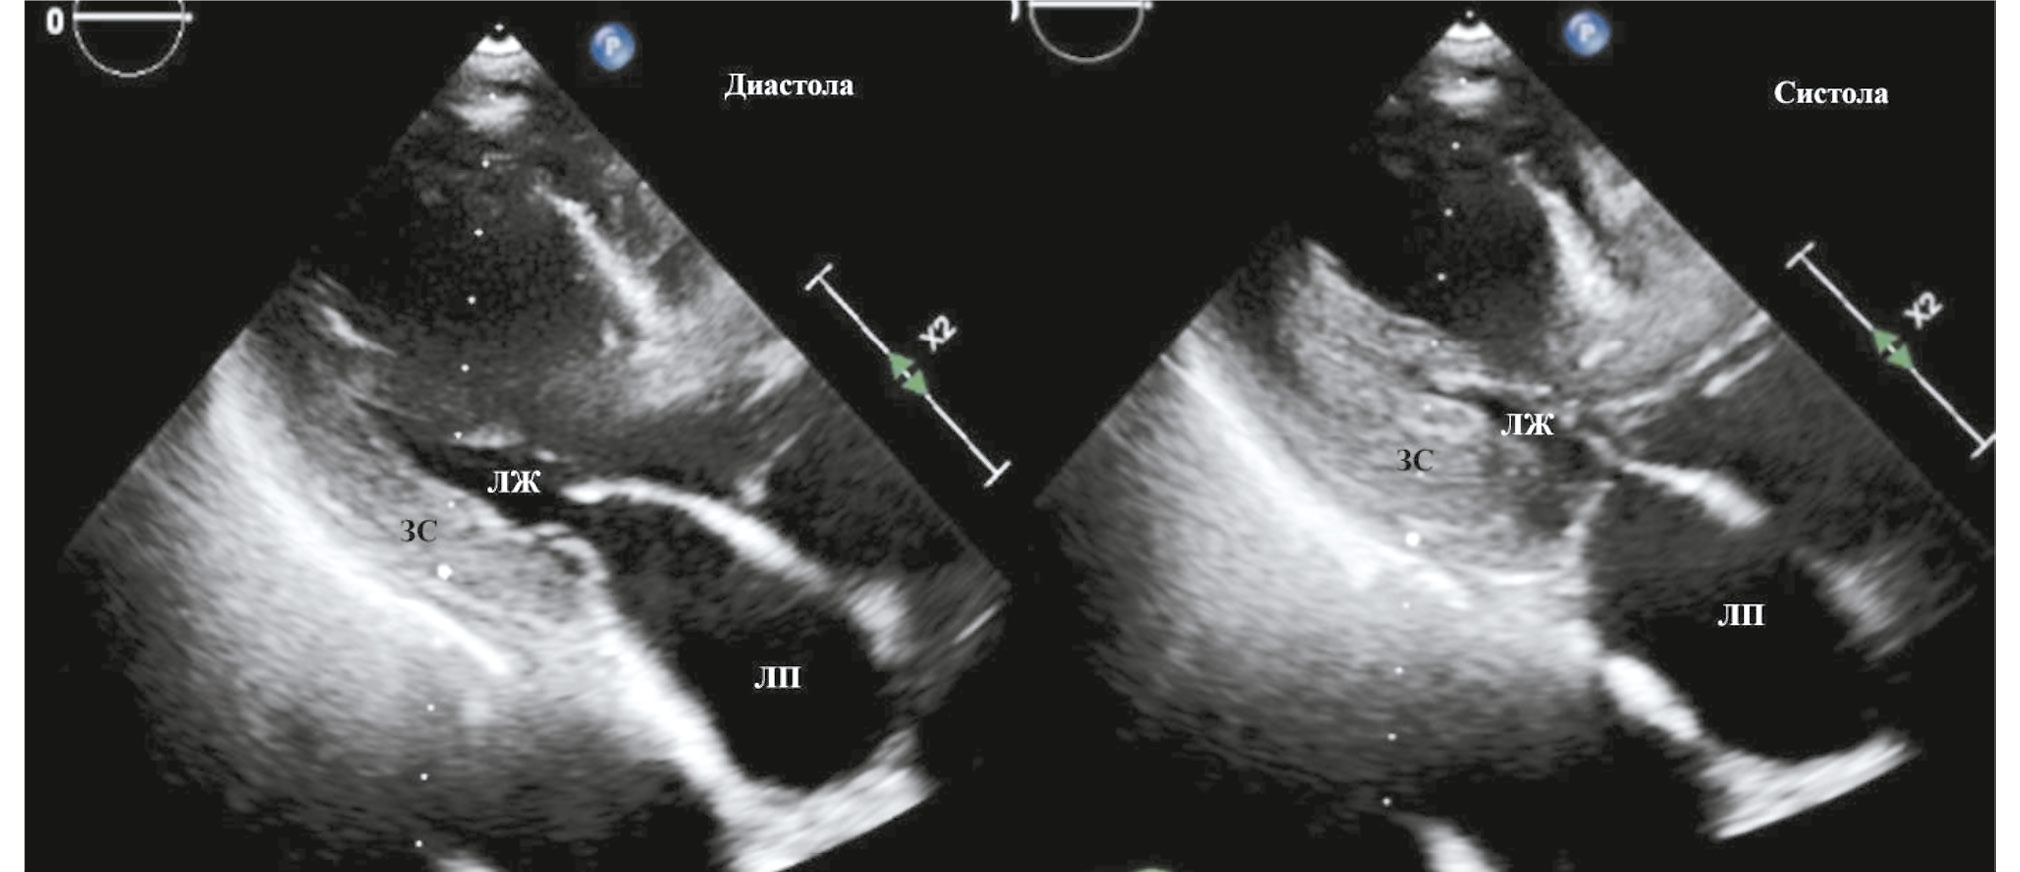

Учитывая несоответствие между клиническим состоянием пациентки и данными КАГ, была одномоментно выполнена вентрикулография: акинезия всех верхушечных сегментов ЛЖ. По окончании КАГ пациентка была направлена в отделение реанимации и интенсивной терапии для дальнейшего дообследования и интенсивной терапии. В день поступления была выполнена эхокардиография (ЭхоКГ): фракция выброса левого желудочка (ФВ ЛЖ) — 40%, толщина задней стенки (ЗС) ЛЖ — 17 мм, толщина межжелудочковой перегородки (МЖП) — 18 мм, акинезия всех верхушечных сегментов ЛЖ с баллонированием верхушки, передне-систолическое движение створки митрального клапана, митральная регургитация II ст., максимальный градиент на выходном тракте ЛЖ — 185 мм рт. ст. (рис. 3, 4).

Рис. 3. Эхокардиография при поступлении (слева — диастола левого желудочка, справа — систола).

Примечание. ЛЖ — левый желудочек, ЛП — левое предсердие, ЗС — задняя стенка левого желудочка.

Fig. 3. Echocardiography upon admission (left — left ventricular diastole, right — systole).

Note. ЛЖ — left ventricle, ЛП — left atrium, ЗС — posterior wall of the left ventricle.